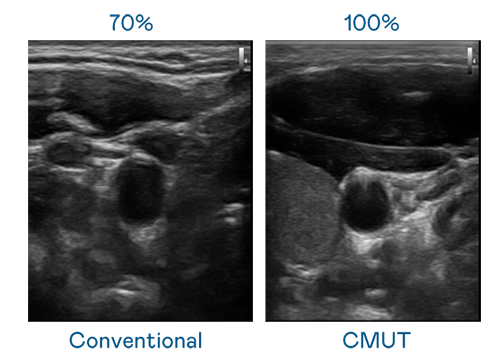

CMUT 技术是一种用电容式微机电元件来产生超音波讯号的技术。与传统 PZT 压电式技术相比,CMUT 频宽增加 30%,更宽频的超音波讯号让影像解析度大幅提升,是实现高影像品质医疗超音波扫描、促进精准医疗发展的关键技术。

超音波影像的解析度高低,首先取决于探头能发出的讯号频宽。w66旗舰厅 CMUT 可提供高清晰的超音波讯号,提供高频宽、高灵敏度、影像纹理细节更高的超音波影像,协助医护人员缩短影像判读时间及利用精准的医疗影像进行诊断。